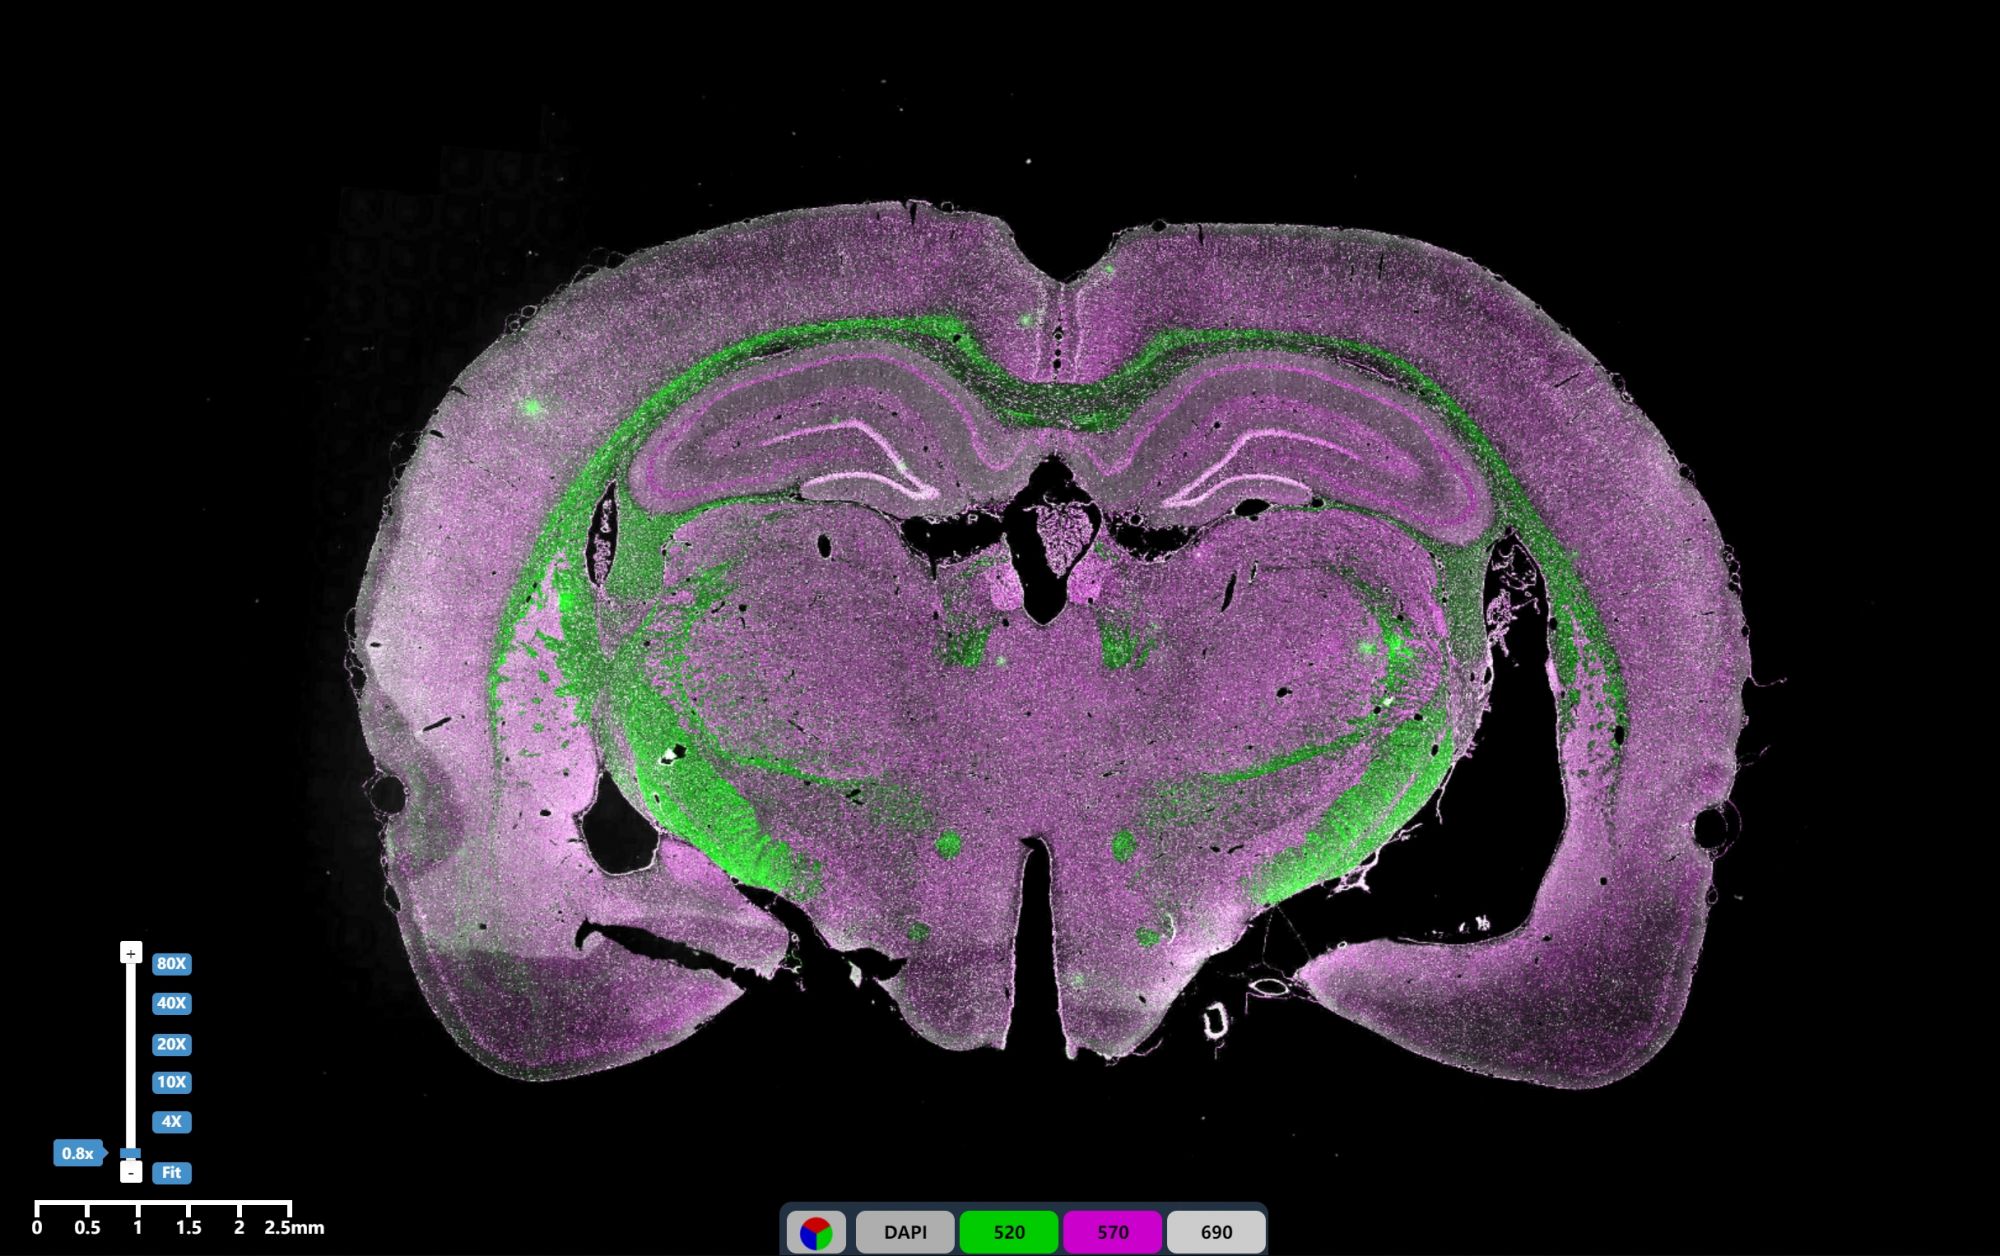

免疫熒光三標腦組織2

IF免疫熒光

免疫熒光三標腦組織